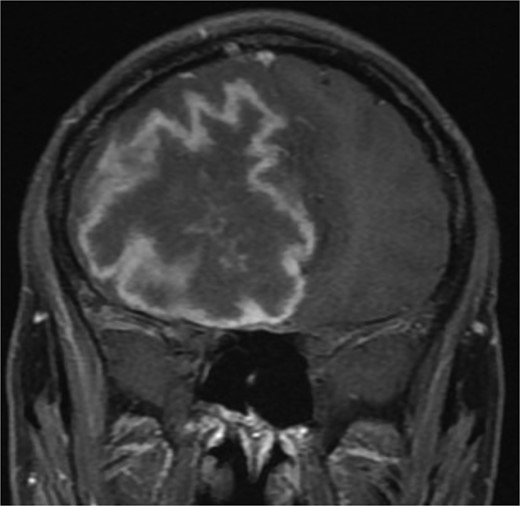

Brain MRI showing right-sided cerebral abscess with midline shift to the left side.

One year later, the patient presented to the emergency department with dizziness, vomiting, and headaches that had started 20 days prior. The CT scan and MRI showed orbital and intracranial invasion. Subsequently, the patient underwent FESS revision with an open craniotomy. The histopathological results revealed findings similar to the first presentation, so the patient was started on intravenous amphotericin B, voriconazole, and dexamethasone. The patient was stable postoperatively until 2 months when he began to deteriorate, and a brain MRI revealed a cerebral abscess (Fig. 4). The patient underwent an urgent open craniotomy with drainage and was shifted to the intensive care unit. However, his condition continued to worsen, and he passed away after 1 month.